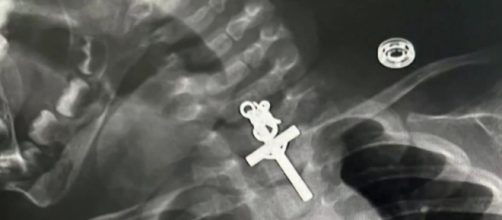

En Perú una niña de 10 meses se tragó un crucifijo. Su madre acudió a un centro de salud con su pequeña en brazos. Rápidamente, los médicos atendieron a la menor. Tras realizar una primera valoración, los médicos del Hospital Víctor Lazarte Echegaray, en la ciudad de Trujillo, se percataron de que la víctima se había tragado un crucifijo. Los especialistas detectaron que el objeto se encontraba en su esófago.

Tras su ingreso, los médicos le realizaron una endoscopia terapéutica a la niña para poder extraer el crucifijo.

La operación tuvo éxito y los médicos extrajeron el objeto que se encontraba en el esófago. Cabe destacar que Maricarmen Sajami Rosas, la madre de la bebé, ha afirmado que no sabía cómo la niña se tragó el crucifijo.

Maricarmen Sajami Rosas reconoció que se dio cuenta de que algo estaba pasando porque la niña sentía molestias desde que estaban en el interior de su casa. Sin embargo, la mujer aclaró que solo se dio cuenta de que su hija se había tragado un crucifijo después que le realizaron varias radiografías. El incidente dejó conmocionados a los ciudadanos peruanos.

El gastroenterólogo Luis Alberto Esteves comentó que tuvieron que esperar 6 horas para que el estómago de la niña estuviera vacío porque había tomado leche. Posteriormente, realizaron la intervención y todo salió bien.